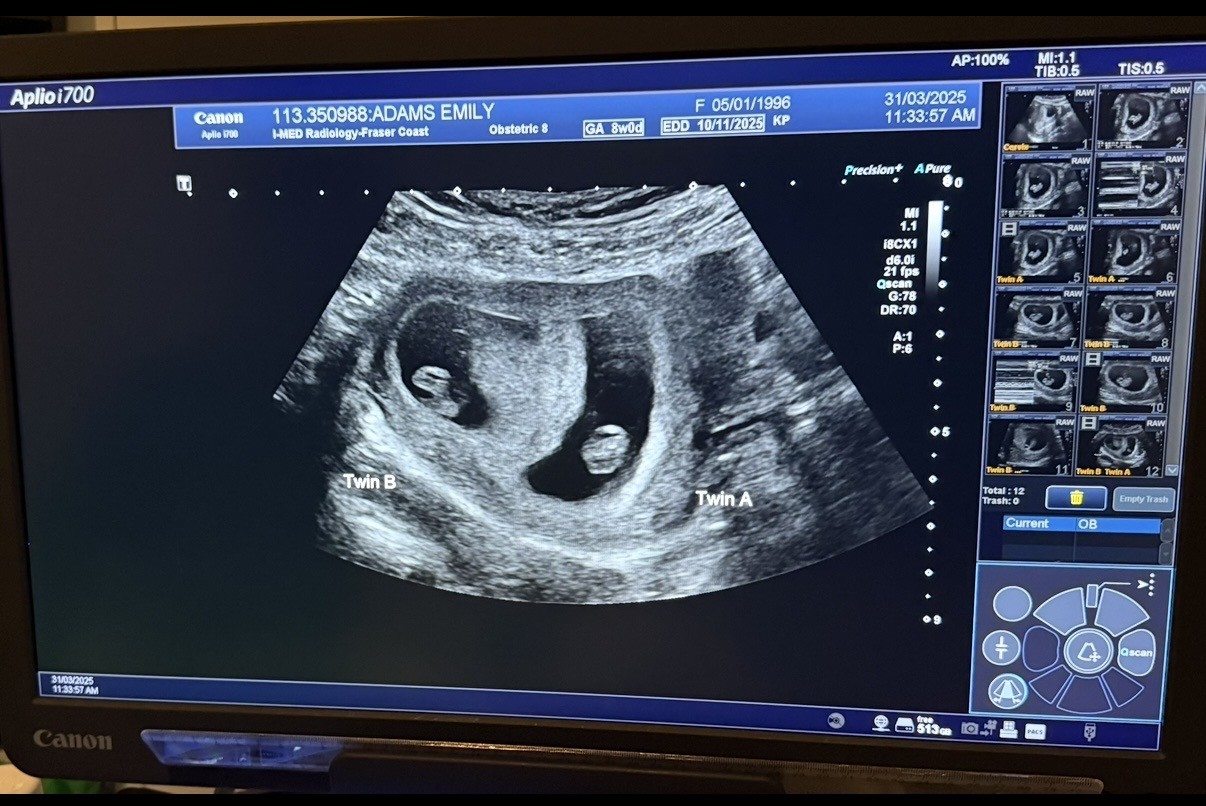

Pictured: Emily's routine ultrascan revealed two embryos.

When a routine ultrasound detected two embryos, the couple’s joy knew no bounds.

“I was stoked,” Andy said. “I was cheering and Emily was crying.”